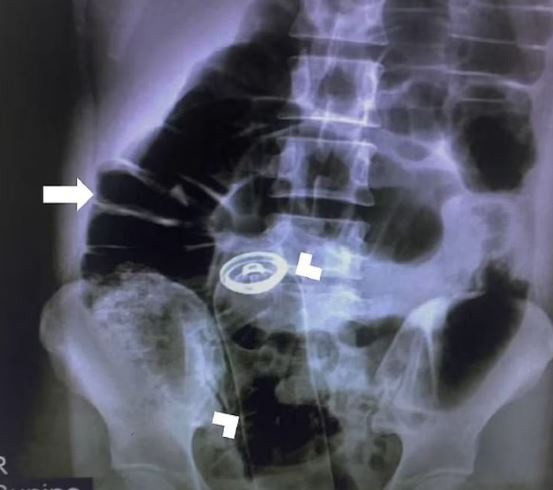

Durumu inceleyen doktorlar herhangi bir kanama ya da kesik olmadığı için genç adama röntgen çektirdi. Röntgen sonuçlarını inceleyen bilim insanları ise resmen şaşkına döndü.

Adamın anüsünden içeri bir deodorant şişesi sokulduğunu ve röntgende şişenin iç organlara dayandığı görülüyor.

Hemen ameliyat kararı alan doktorlar, adamın karnını keserek büyük boy deodorant şişesini aldı. Operasyonun iki saat sürdüğü belirtilirken, deodorant kutusunun nasıl girdiği ise açıklanmadı. İsmi açıklanmayan hastanın vakası “Visual Journal of Emergency Medicine” isimli tıp dergisinde yer aldı.